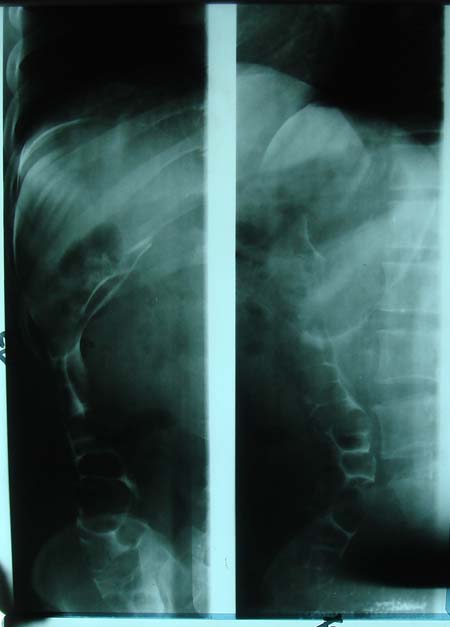

以下是引用dyqct在2009-8-23 16:17:00的发言:[br]考虑:1、造影剂进入腹腔、结肠旁沟、肝周;[br] 2、子宫明显增大(腺肌增生症?);[br] 3、膀胱显影是由于造影剂吸收后经肾分泌进入膀胱的;[br] 4、建议mri检查子宫。